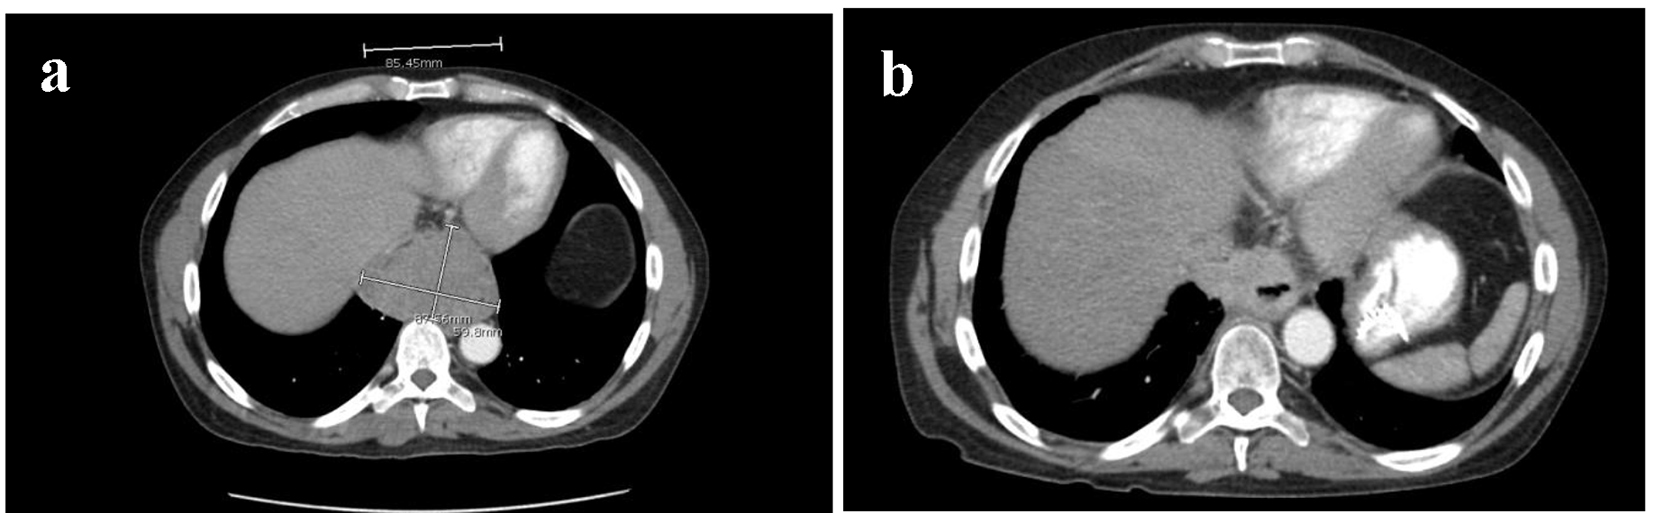

Initial imaging included computed tomography (CT) with oral and intravenous (IV) contrast of the chest which illustrated a posterior mediastinal soft tissue mass with necrosis measuring 6.0 × 8.8 cm abutting but not encasing the distal thoracic esophagus (Fig. 1a) [4]. Two prominent hypodense lesions were localized in the right posterior hepatic lobe measuring 2.6 × 2.8 × 2.9 cm and the medial segment of the left hepatic lobe measuring 1.6 cm in diameter (Fig. 2a) [4].

Figure 1. (a) Sagittal section of CT thorax with oral and IV contrast measuring posterior mediastinal mass prior to chemoradiation with dimensions of 6.0 × 8.8 cm. (b) Sagittal section of CT thorax with oral and IV contrast of posterior mediastinal mass after 10 cycles of CVD. Tumor size decreased to 5.5 × 3.0 × 4.0 cm.

The patient completed 10 cycles of chemotherapy and experienced a gradual improvement in his back pain, weight, appetite, swallowing, and performance status throughout treatment. Follow-up CT scans after the 10th cycle showed near complete response of the tumor and a decrease in size of the hepatic lesions. CT scan with IV and oral contrast measured the mediastinal mass to be 5.5 × 3.0 × 4.0 cm (Fig. 1b) [5]. The posterior right hepatic lobe lesion decreased in size to 2.6 × 2.8 × 2.9 cm, and the left hepatic lobe lesion completely resolved (Fig. 2b) [5]. These interval decreases in the hepatic metastasis corresponded to a partial response per response evaluation criteria in solid tumors (RECIST) criteria [6]. The patient finished a total of 12 cycles of chemotherapy with subsequent resolution of the primary mass and the hepatic lesions, thus corresponding with a complete response per RECIST criteria.

To our knowledge, this is the first reported case of combination CVD therapy and Y90 radioembolization for metastatic malignant paraganglioma. Our patient thus far has demonstrated remarkable clinical and radiological improvement with 10 cycles of the CVD regimen. Follow-up CT scans demonstrated a progressive decrease in tumor size throughout chemotherapy cycles. The decrease in size of the posterior mediastinal mass is likely attributed to a similar chemotherapy schedule as demonstrated previously in prior studies [9, 10]. The patient has demonstrated a decrease in the dominant metastatic liver lesions shortly after radioembolization of both the right and left hepatic arteries (Fig. 2a, b). The RECIST criteria monitor the imaging response to treatment of solid tumors. By applying this model’s calculation to this case, we have calculated a 58% decrease in the patient’s metastatic liver lesions. This corresponds with a complete response per RECIST criteria [6]. The most recent imaging studies after 12 cycles of chemotherapy and localized radiation therapy with Y90 radioembolization have shown complete remission of the primary posterior mediastinal tumor as well as all hepatic lesions to date.